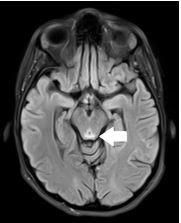

妊娠剧吐相关韦尼克脑病:一例报告

The patient was a 22-year-old female 13 weeks pregnant presenting to the emergency department (ED) with neurological deficits after several weeks of hyperemesis gravidarum requiring hospitalization. Exam and workup ultimately revealed the diagnosis of Wernicke encephalopathy. Her symptoms improved after administration of thiamine.

Wernicke encephalopathy is a consequence of thiamine deficiency, commonly seen in patients with alcohol use disorder but also with other causes of nutritional deficiency, such as hyperemesis gravidarum. Wernicke encephalopathy is a clinical diagnosis that requires a high degree of suspicion and is, therefore, often missed in the ED setting. Treatment is supplemental thiamine and management of the root cause for nutritional deficiency.

MR imaging findings in alcoholic and nonalcoholic acute Wernicke's encephalopathy: a review.酒精性和非酒精性急性韦尼克脑病的磁共振成像表现:综述

Biomed Res Int. 2014;2014:503596. doi: 10.1155/2014/503596. Epub 2014 Jun 24.